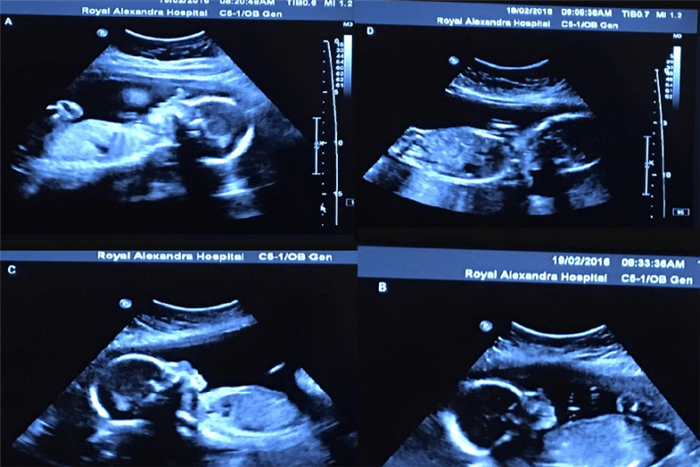

Nel dicembre scorso Bethany e Tim Webb hanno scoperto di essere in attesa “la persona che stava facendo gli ultrasuoni ha girato lo schermo e ha contato 4 bambini”.

“Sono stata felice del fatto che fossi sdraiata perché non riuscivo a credere che ci fossero 4 piccine lì dentro. Ho pensato che ci fosse qualche errore, mio marito è quasi svenuto, si è dovuto sedere un momento” ricorda Bethany, la mamma delle 4 bambine.